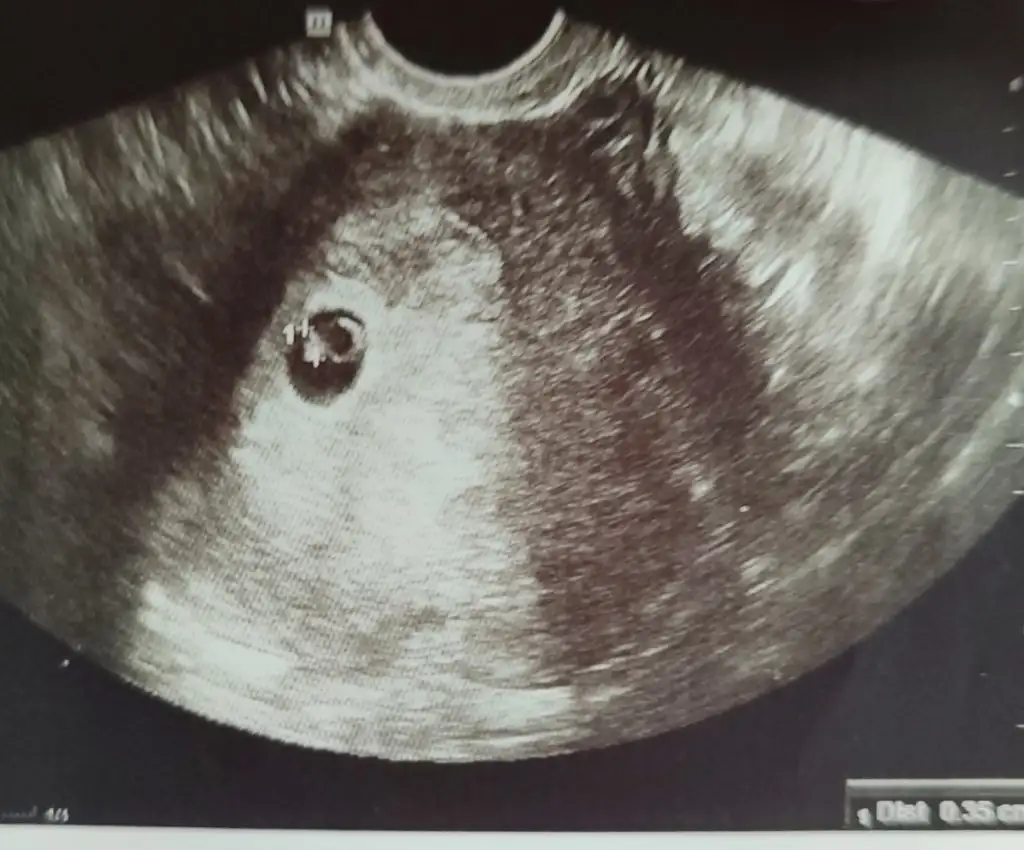

Canım konunu şimdi gördüm. Nasılsın iyi misin? 2. 3. Doktor görüşü daha al. İnşallah sağlıcakla duyarsın kalp atışını tekrar doktora gidersen haber verKızlar merhaba burda saolsun kızlar çok yardımcı oldu ama basına gelen varmı sata göre 7+3 ama geç döllenme oldu bugün kalp atısına gıttım bebek çok küçük altı hafta kadarlık kalp atısı yok bu hafta ıcı mutlaka kürtaj ol dedı bunu dıyen klınıkte kı doktorum çok uzuldum 2-3 mm dedı bebek sizce kese bozulmazmı öyle olsa kanama vs yok yolk yerınde yanı aklımı çıldıracaammm

Canım bayram sonu çok geç ya, başka doktora gitsen ya hafta içiAh dünden berı geberıyorum sanıyorum resmen rüyamda dahı zorla kürtaja alınıyordum zor ama doktor bu acımasızlıgı daha zor bundan sonra surecı de bılmıyorım bebek 6 haftalık kalp atışı yok beklemek ıstemedı dırek kürtaj ol hafta ıcı bır ay sonra yenıden tedavıye baslayalım dedı ben kürtaj olmak istemiyorum herşeyi yolunda bebek var yolk düzgün kese düzgün bebek uyumlu ama kalp yok ne yapacağımı bılmıyorım beklemek ıstıyorım bayram sonuna kadar

Başka doktora gidin haftaya mutlaka gerekirse vajinal olarak dinlesinler gec dollenmede duyamamaları normal anormal olan doktorunuz benceKızlar merhaba burda saolsun kızlar çok yardımcı oldu ama basına gelen varmı sata göre 7+3 ama geç döllenme oldu bugün kalp atısına gıttım bebek çok küçük altı hafta kadarlık kalp atısı yok bu hafta ıcı mutlaka kürtaj ol dedı bunu dıyen klınıkte kı doktorum çok uzuldum 2-3 mm dedı bebek sizce kese bozulmazmı öyle olsa kanama vs yok yolk yerınde yanı aklımı çıldıracaammm

Vajınal de de duyamadı dınledı yoksa bır kere baktı kalp atısı yok dedı karından çok derınden bır ses duyduk ama o senin kalp atısındır dedıBaşka doktora gidin haftaya mutlaka gerekirse vajinal olarak dinlesinler gec dollenmede duyamamaları normal anormal olan doktorunuz bence

Çarşamba başka doktora randevu oluşturdum sata 8+1 oluyorum o güne bebek gelısmıs ise unçmut var ama gelişim yok ise boşa beklersın dedı doktorSakın acele etme geç oluşabiliyor ben çok gördüm böyle o yüzden bekle beklemenin sana bir zararı yok benim doktorum öyle demişti beni kürtaj dedikten sonra iki hafta daha gelişmesi için şans tanımıştı benim gelişmedi kürtaj oldum orası ayrı ama acele etme beklemenin bir zararı yok